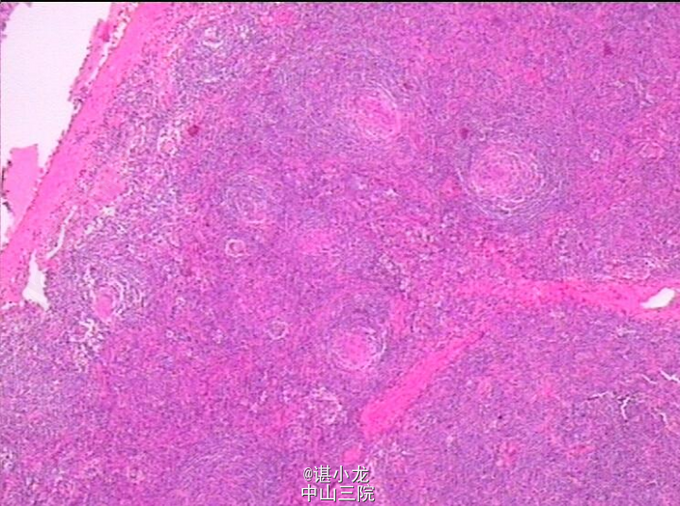

诊断:腹膜后肿物 治疗:腹膜后肿物切除术 手术简要过程:麻醉成功后,取平卧位,术野皮肤常规消毒,铺巾;取左侧经腹直肌外缘切口,长约15cm ,逐次切开皮肤,皮下组织,电刀止血,电刀切开腹直肌和腹直肌前后鞘,切开腹膜;打开胃结肠韧带,探查见胰体尾部胰腺后方存在一约4*2cm大小实性肿物,与周围组织粘连,遂决定行腹膜后肿物切除术。分离肿物与周围粘连,暴露最低部位,在肿物最低处见多个动脉供应,沿着动脉解剖分离周围组织,见改血管丛由肠系膜根部发出。打开肠系膜,将血管与周围组织分离,并用4#将血管结扎切断。再次游离肿物,将肿物完整游离切下。之后将打开的肠系膜按原位缝合。检查无活动性出血后,彻底清洗腹腔。清点器械无误后逐层关腹。切除组织送病理。病理回报Castleman Disease。

巨淋巴结增生是一种罕见的良性淋巴节增生性疾病,可发生于任何年龄,甚至可发于婴幼儿,成年人发病多见,最常见单发型CD ,多发型则相对少见。本病的起源是由于免疫调节缺陷导致的淋巴结中B淋巴细胞及浆细胞的过度增生,免疫学的研究证实CD发病可能与病毒感染有关。CD病理学分为三个主要类型:1)透明血管型2)浆细胞型3)混合型。90%的单中心型CD是透明血管型 ,表现为病变淋巴结滤泡增生和滤泡间小血管增生及透明性变,部分小淋巴细胞围绕生发中心呈环层状排列(似洋葱皮样结构)。手术切除目前为止被认为是单中心型CD的最合适治疗方法,部分无法切除患者可选择放化疗等方法。手术治疗方面,由于CD多有丰富的血供且周围解剖结构复杂,多紧邻血管神经,因此CD的手术治疗需要做好充足的术前准备。术前全面的影像学检查、充分备血对于手术治疗CD十分必要。化放疗方面,无统一的化疗方案,部分化疗方案如CHOP化疗方案等取得了良好的效果,采取放疗的方式治疗无法手术切除的单中心型CD也取得了良好的效果。